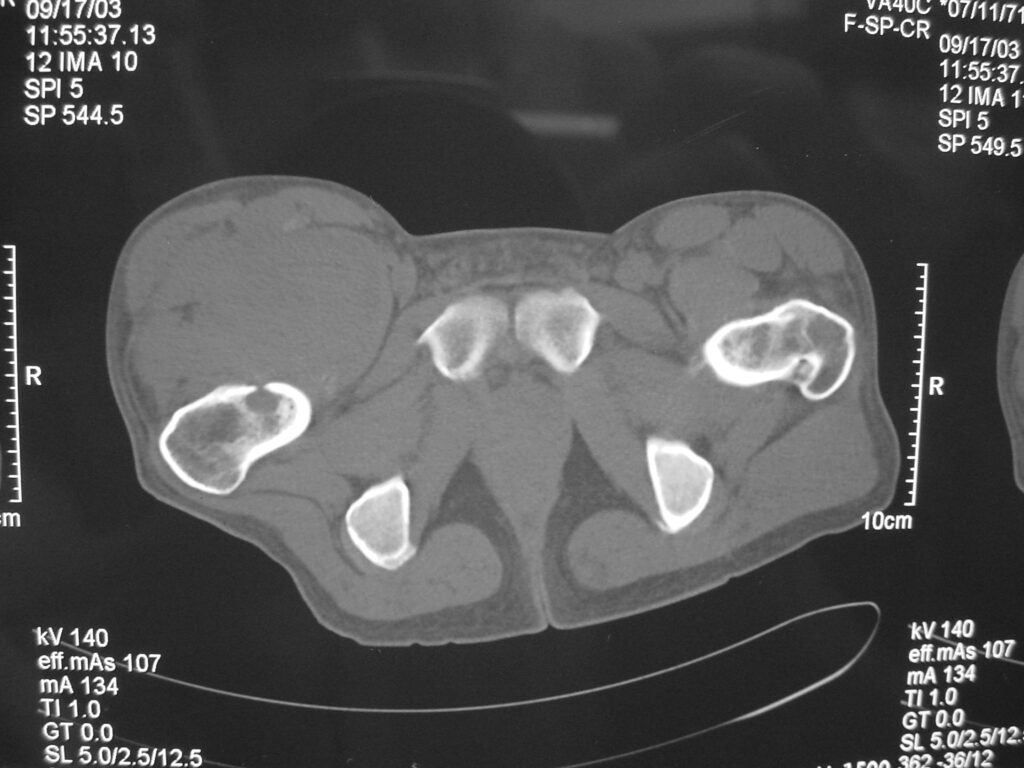

RADIOGRAPHIC PRESENTATION

X-rays

Normal in approximately 50% of the cases.

Soft tissue density with mineralization in 30% of cases. This type of mineralization usually presents as calcifications with an irregular contour often in a peripheral distribution.

In 11% to 20% of cases there may be a periosteal reaction, adjacent bony erosion or bone invasion.